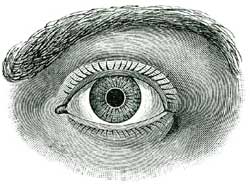

| XXV. | How we Hear, See, Smell, Taste; and Feel | 138 |